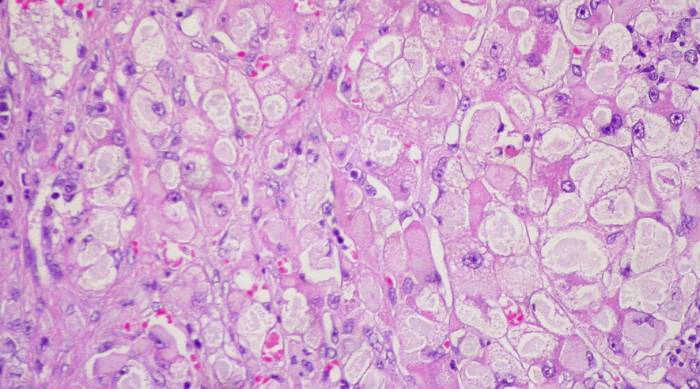

Гепатоциты — крупные клетки, имеющие форму шестиугольника, реже — полигонального многоугольника. Содержат от 1 до нескольких ядер. От того, как выглядит клетка печени, напрямую зависит ее качество: многоядерные полигональные клетки более функциональны и отвечают за приспособительные функции железы.

Васкулярную часть клетки печени покрывают микроскопические ворсинки. Они внедряются в капилляр, обеспечивая прямой контакт с кровью. В пространстве между микроворсинками и просветом кровеносного сосуда располагаются отростки клеток Купфера (печеночных макрофагов).

Полноценного тканевого барьера между гепатоцитами и капиллярами нет. Это позволяет веществам, синтезируемым в печени, поступать непосредственно в кровь. По этой причине питательные и токсичные вещества железа также захватывает напрямую из биологической жидкости.

Билиарная сторона клетки печени направлена в сторону желчного капилляра. Эта часть гепатоцита отвечает за выработку одного из основных пищеварительных соков — желчи. Через капилляр фермент поступает в отводящие потоки. При нормальном состоянии печени желчь в кровь не поступает, так как тело гепатоцита служит естественным барьером между желчным и кровеносным сосудами.